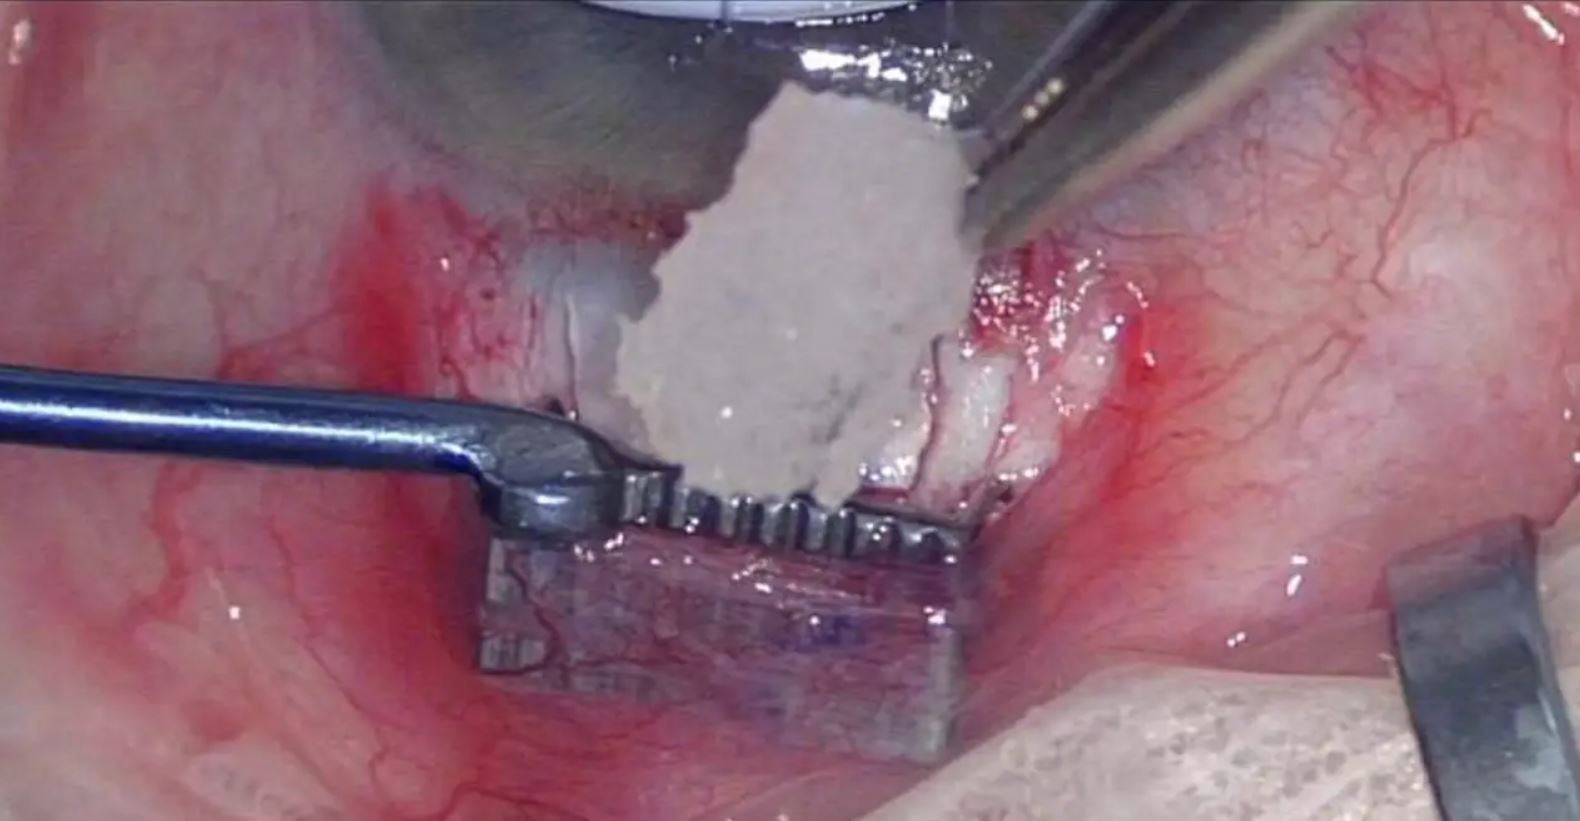

Antimetabolites in filtration surgery

Tips & Tricks for Trabeculectomy

Graham Lee